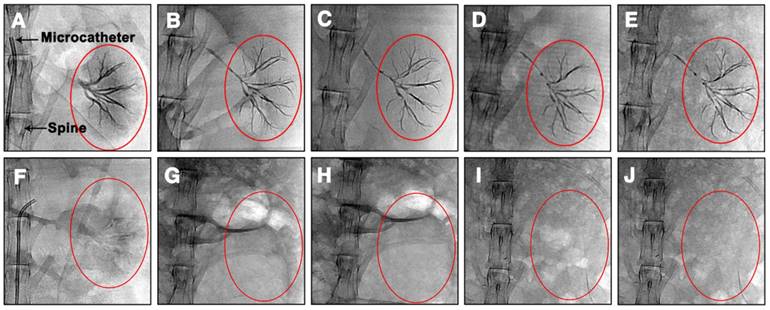

Figure 2

X-ray images of the embolization process in the renal artery of rabbits using Ta@CaAlg microspheres.

Generally, embolic agents are normally mixed with iodinated contrast media and injected into the target area during the TACE procedure. However, these contrast media cannot relay the exact site deposited by embolic agents because of their rapid diffusion following administration. In this study, “2-in-1” Ta@CaAlg microspheres could be injected into the renal arteries of normal rabbits without the need for a separate contrast media. In vitro experiment, the relative signal intensities of 10% Ta@CaAlg microspheres acquired on IVIS Lumina XR imaging system was 6490 whereas that of Iodixanol solution was 7355. Clinical imaging modalities showed the real-time location and distribution of the microspheres directly. Figure 2 shows images of the embolization process in the renal artery of rabbits using Ta@CaAlg microspheres. Figure 2B shows that the Ta@CaAlg microspheres were injected from the microcatheter into the largest artery, and Figure 2C-D shows that they reached all the large arteries. Figure 2E-F illustrates that the microspheres also reached the small arteries. As a result, all size levels of renal arteries were embolized by the Ta@CaAlg microspheres. The whole process was clearly and precisely exhibited on the clinical imaging modalities.